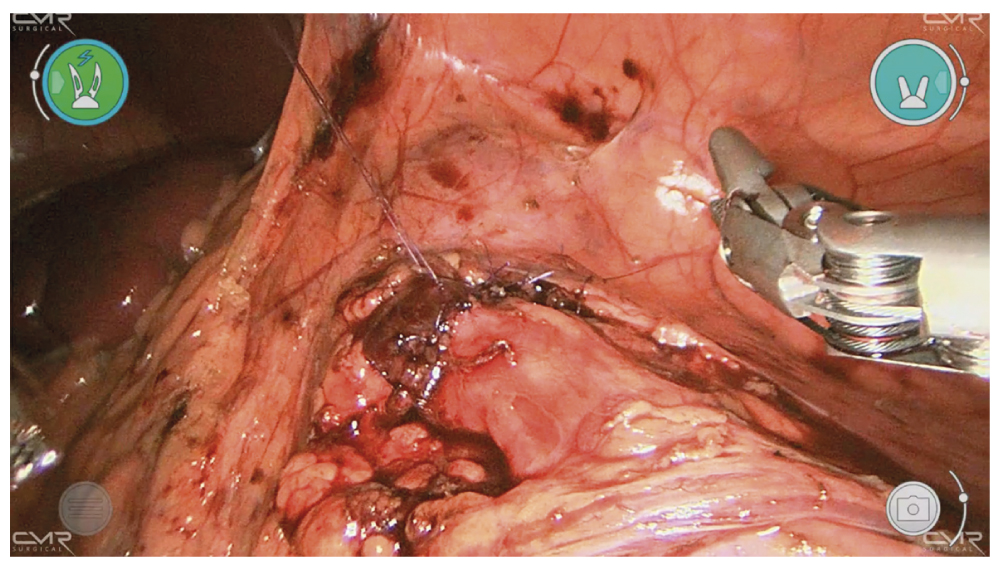

На переднюю стенку мочеточника наложено 2 транспариетальных якорных шва, предназначенных для его стабилизации. Затем сразу над камнем с использованием холодных ножниц выполнялась продольная уретеротомия длиной 2 см с заходом вверх за стриктуру мочеточника (рис. 3).

Рис. 3. Робот-ассистированная уретеролитотомия. Этап рассечения мочеточника.

Fig. 3. Robot-assisted ureterolithotomy. Ureter dissection.